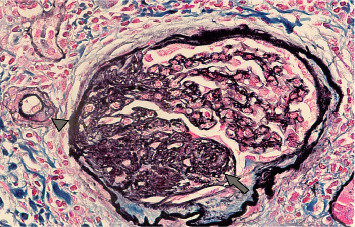

Proteinuria in a patient with long-standing Type 1 diabetes mellitus (T1DM) usually suggests diabetic kidney disease (DKD). However, DKD occurs late in the disease and is associated with hypertension and retinopathy. We report an adolescent with T1DM who, 1 year after initial diagnosis, developed nephrotic syndrome (NS). He was treated with steroids but developed frequent relapses and became steroid-dependent. A subsequent kidney biopsy revealed minimal change disease (MCD) and mild DKD. He was treated with mycophenolate mofetil (MMF) and remains in remission. Primary podocytopathy, such as MCD, is a rare cause of NS in a patient with T1DM. Indications for kidney biopsy and treatment options are similar to those of other children with a diagnosis of NS. This report highlights that, although rare, primary glomerulopathy can occur in pediatric diabetic patients and should be considered in the differential diagnosis of proteinuria, as early recognition and intervention can lead to favorable outcomes.

Abstract Image